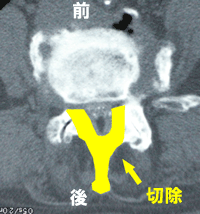

椎弓切除2

C.椎弓切除2

を広げる方法です。右図Cのように、片方から椎弓の一部を切除して

中をくり抜くようにします。このメリットは、小さい切開なので筋肉へ

のダメージが少ないこと、椎弓の一部が残っているので瘢痕が神経

を押さえることが少ないこと、などです。また、別の施設では椎弓を